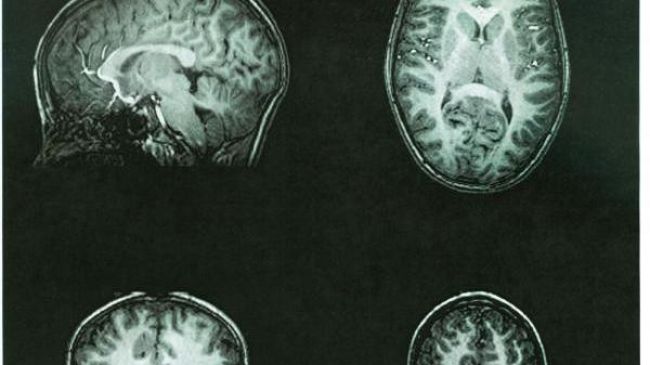

اكتشاف عصب يشعر بالخطر قبل حدوثه بـ200 جزء من الثانية